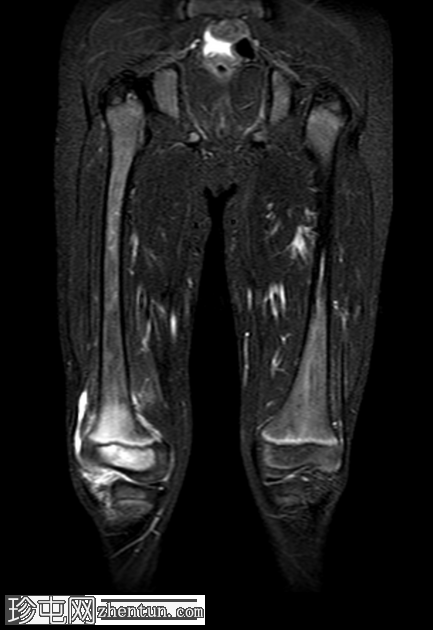

冠状位

STIR序列

骨盆STIR序列(大视野)显示病变位于右膝。

右膝专用MRI显示股骨外侧髁后方髓内有一边界清晰的病灶,大小为1.6 x 0.9 cm,中心T1呈低信号,T2/STIR呈高信号,周围可见薄层T1高信号环(半影征)。

周围骨髓水肿广泛,在STIR序列上呈高信号,在T1加权像上呈低信号。